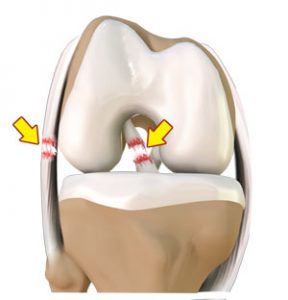

PATELOFEMORAL

S. PATELOFEMORAL